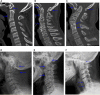

Results: A total of 718 Klippel-Feil syndrome patients, including 327 men and 391 women, with an average age of 46.8 years were enrolled. According to the Samartzis classification scheme, 621 cases (86.5%) were classified as type I, 48 cases (6.7%) were classified as type II, and 49 cases (6.8%) were classified as type III, respectively. The most commonly fused segments were C2-3 (54.9%) and C5-6 (9.3%). Of all 718 patients, 133 (18.5%) patients underwent surgical treatment, mainly via the posterior approach (69.9%). The clinical factors included age, gender, deformity, instability, and Samartzis classification. Men were more likely to require surgical treatment (p < 0.001). Patients with instability (p < 0.001) or patients with deformity (p = 0.004) were also more likely to undergo surgery. All three of these variables were included in the binary regression analysis. Finally, gender (p < 0.001) and unstable joints (p < 0.001) were identified to be independently associated with surgical treatment. Gender was the most important risk factor with men being 2.39 times more likely to have surgical treatment, while patients with instability were 2.31 times more likely to receive surgery.

Conclusion: The prevalence of patients with Klippel-Feil syndrome requiring surgery was 18.5%, with the majority undergoing posterior cervical surgery. Gender and instability were indemnified as independent risk factors leading to surgical treatment.